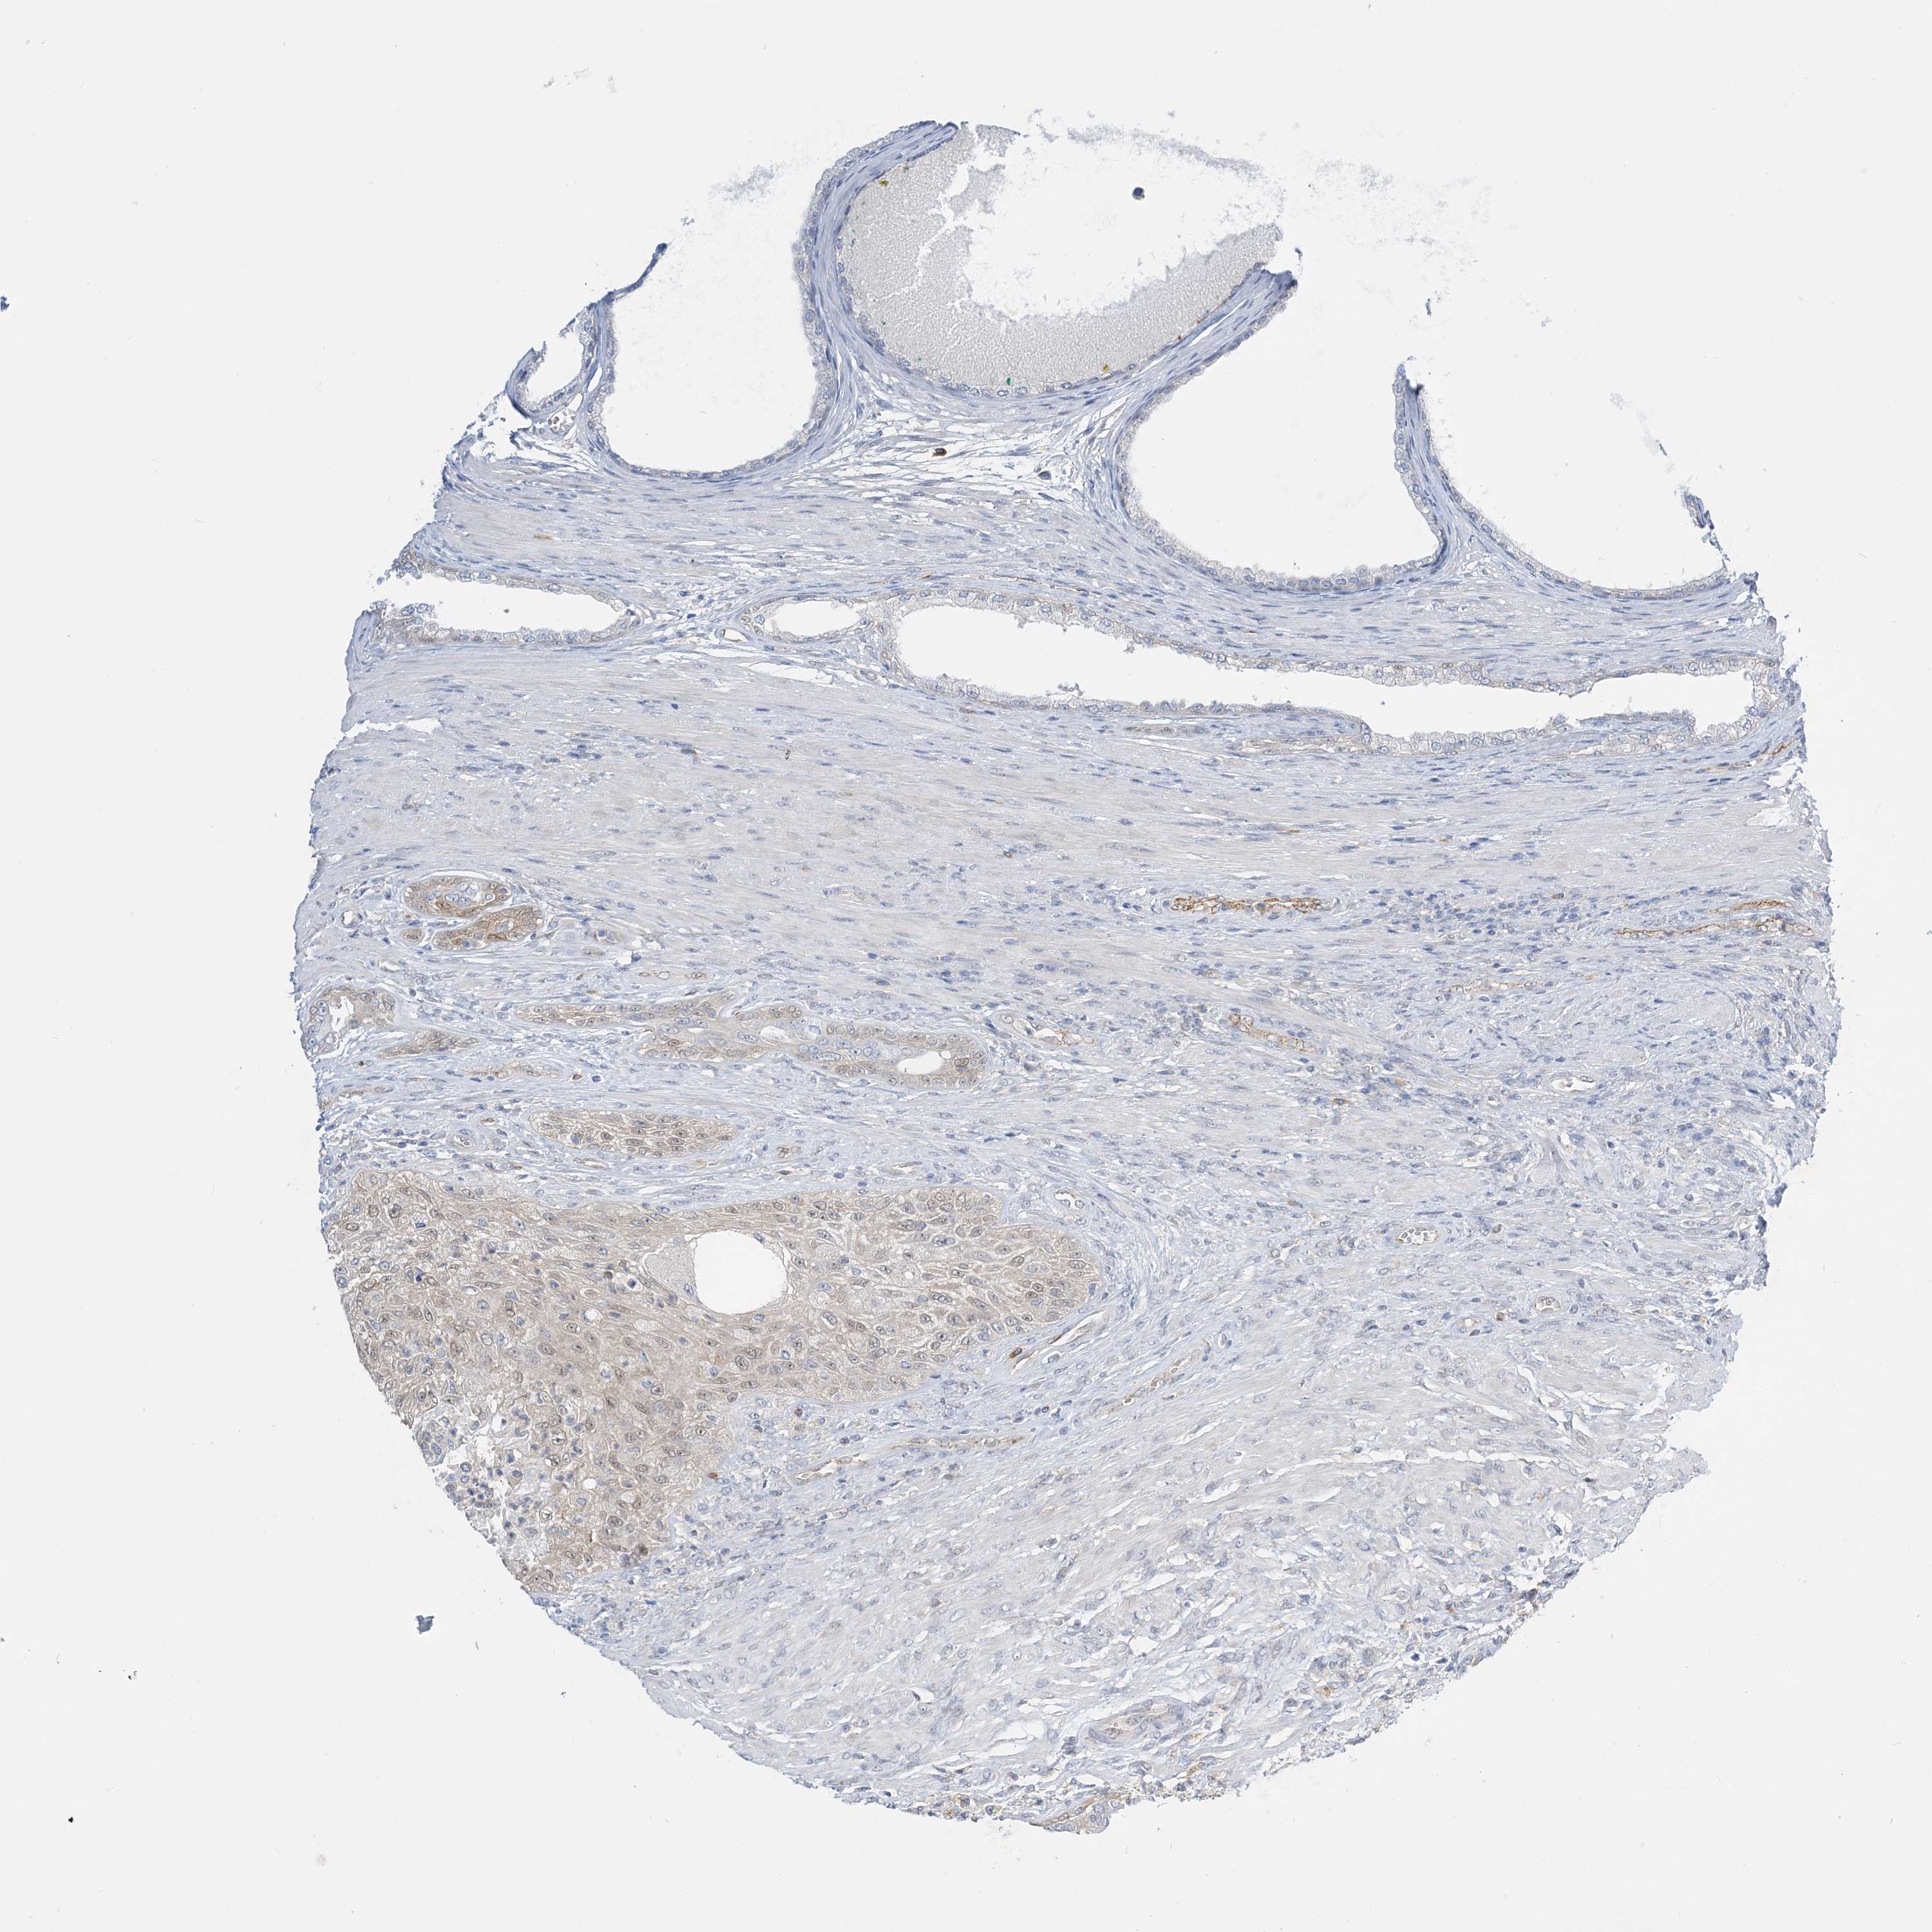

PROSTATE CANCER - Protein expressioni

A mouse-over function shows sample information and annotation data. Click on an image to view it in a full screen mode. Samples can be filtered based on level of antibody staining by selecting one or several of the following categories: high, medium, low and not detected. The assay and annotation is described here.

Antibody stainingi

Antibody staining in the annotated cell types in the current human tissue is reported as not detected, low, medium, or high, based on conventional immunohistochemistry profiling in selected tissues. This score is based on the combination of the staining intensity and fraction of stained cells.

Each image is clickable and will lead to virtual microscopy that enables deeper exploration of all samples and also displays staining intensity scores, fraction scores and subcellular localization as well as patient and tissue information for each sample.

Antibody HPA036698

Antibody HPA036699

Staining

High

Medium

Low

Not detected

Intensity

Strong

Moderate

Weak

Negative

Quantity

>75%

75%-25%

<25%

None

Location

Nuclear

Cytoplasmic/membranous

Cytoplasmic/membranous,nuclear

Adenocarcinoma, High grade

Adenocarcinoma, Low grade